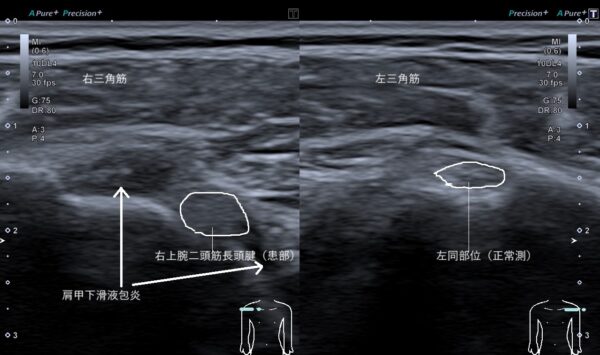

超音波画像観察を行うと上腕二頭筋長頭腱(肘を曲げる筋肉の腱)が腫れていました(画像、白線で囲んだ丸の比較)。

また、その周囲は滑液(筋肉や関節の動きをスムーズにする)が炎症(傷ついた組織を修復させる生体反応)によって過剰にたまっていました(画像、矢印の先の黒い箇所)。